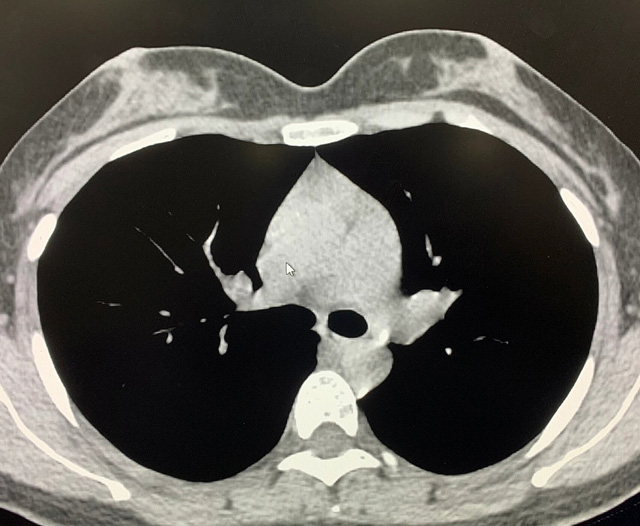

能譜純化技術(shù)的核心是通過物理濾過(如錫濾片)或軟件算法,選擇性濾除低能X射線光子,保留高能光子。在胸部低劑量CT掃描中顯著提升了圖像質(zhì)量與輻射劑量的平衡。

優(yōu)勢輻射劑量顯著降低相較于常規(guī)CT,輻射劑量減少約70%-90%,尤其適合需多次隨訪的高危人群(如肺癌篩查),降低輻射相關(guān)癌癥風(fēng)險早期肺癌篩查效果明確可清晰檢測毫米級肺結(jié)節(jié),顯著提高早期肺癌檢出率,降低死亡率。檢查快捷且普及性高單次掃描僅需數(shù)秒,無需對比劑,設(shè)備廣泛配置于基層醫(yī)院,便于大規(guī)模篩查。長期成本效益顯著雖單次費用與常規(guī)CT相近,但早期干預(yù)可大幅降低晚期治療費用及社會醫(yī)療負(fù)擔(dān)。技術(shù)優(yōu)化提升圖像質(zhì)量迭代重建算法(如ASIR、MBIR)在降低劑量同時減少噪聲,平衡影像質(zhì)量與安全性。